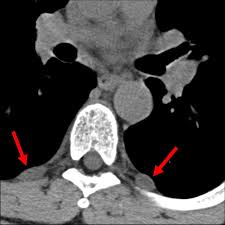

Surgeons carefully remove your schwannoma while taking care to preserve nerve fascicles that arent affected by your tumor. Rarely nerve sheath tumors can be malignant. On conventional MRI and diffusion-weighted imaging DWI MPNSTs and BPNSTs showed significant differences in tumor size margin presence of perilesional edema and absence of split fat fascicular.

On conventional MRI and diffusion-weighted imaging DWI MPNSTs and BPNSTs showed significant differences in tumor size margin presence of perilesional edema and absence of split fat. View chapter Purchase book.

Results of this limited experience indicate linear acceleratorbased spinal radiosurgery is feasible for treatment of benign nerve sheath tumors. Most benign nerve sheath tumors need no treatment other than observation which involves following up with repeat physical examinations and serial imaging. This of course means that surgery is required. On conventional MRI and diffusion-weighted imaging DWI MPNSTs and BPNSTs showed significant differences in tumor size margin presence of perilesional edema and absence of split fat fascicular. Some nerve sheath tumors are treated with surgery. On conventional MRI and diffusion-weighted imaging DWI MPNSTs and BPNSTs showed significant differences in tumor size margin presence of perilesional edema and absence of split fat. Rarely nerve sheath tumors can be malignant.